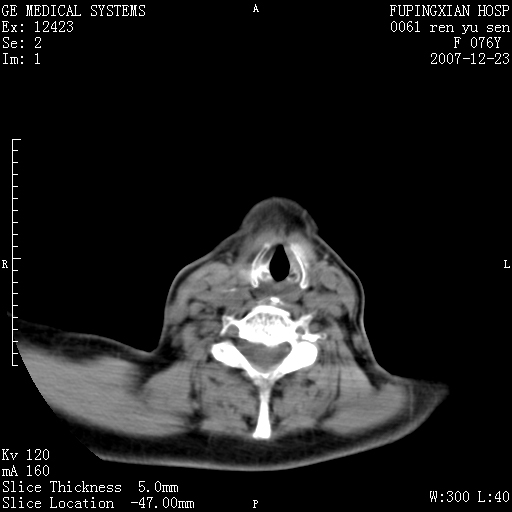

男性 76岁 下颌右侧磨牙区肿物数月, 约2.0*1.5cm大小波及颊舌侧,伴颌下淋巴结肿大。余(-)

右颈部颌下腺前可见一类圆形软组织密度影,密度不均,内见小片坏死区.颌下颈前可见两枚肿大淋巴结影.考虑淋巴结感染可能性大,建议增强扫描..

右侧第四磨牙缺失,局部牙槽骨质破坏,边界欠清晰,同侧颌下及竟不见多发肿大淋巴结显示。考虑肿瘤病变可能性大,感染待排